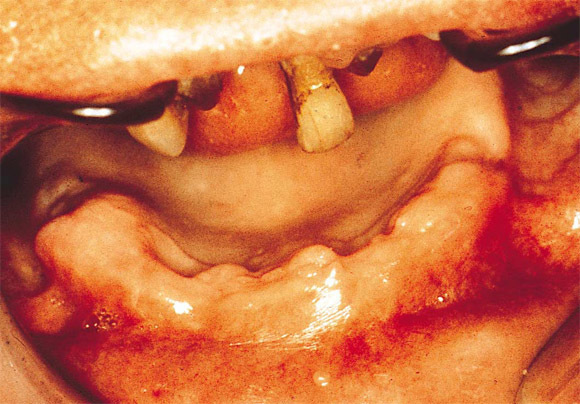

Stomatite

Stomatite des dentiers.